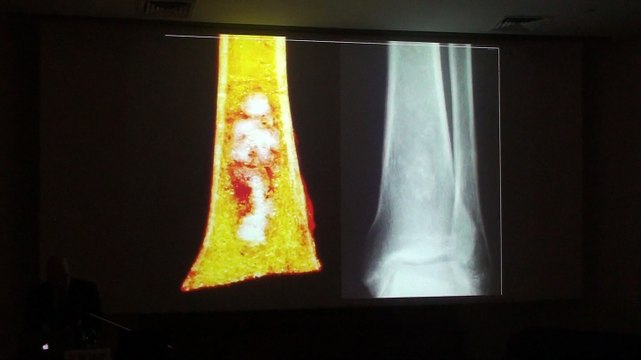

Incidential Osseous Lesions - Mark J. Kransdorf

Uploaded: June 17, 2015 Views: 7

Pediatric Musculoskeletal Infections - Tal Laor

Uploaded: June 17, 2015 Views: 5